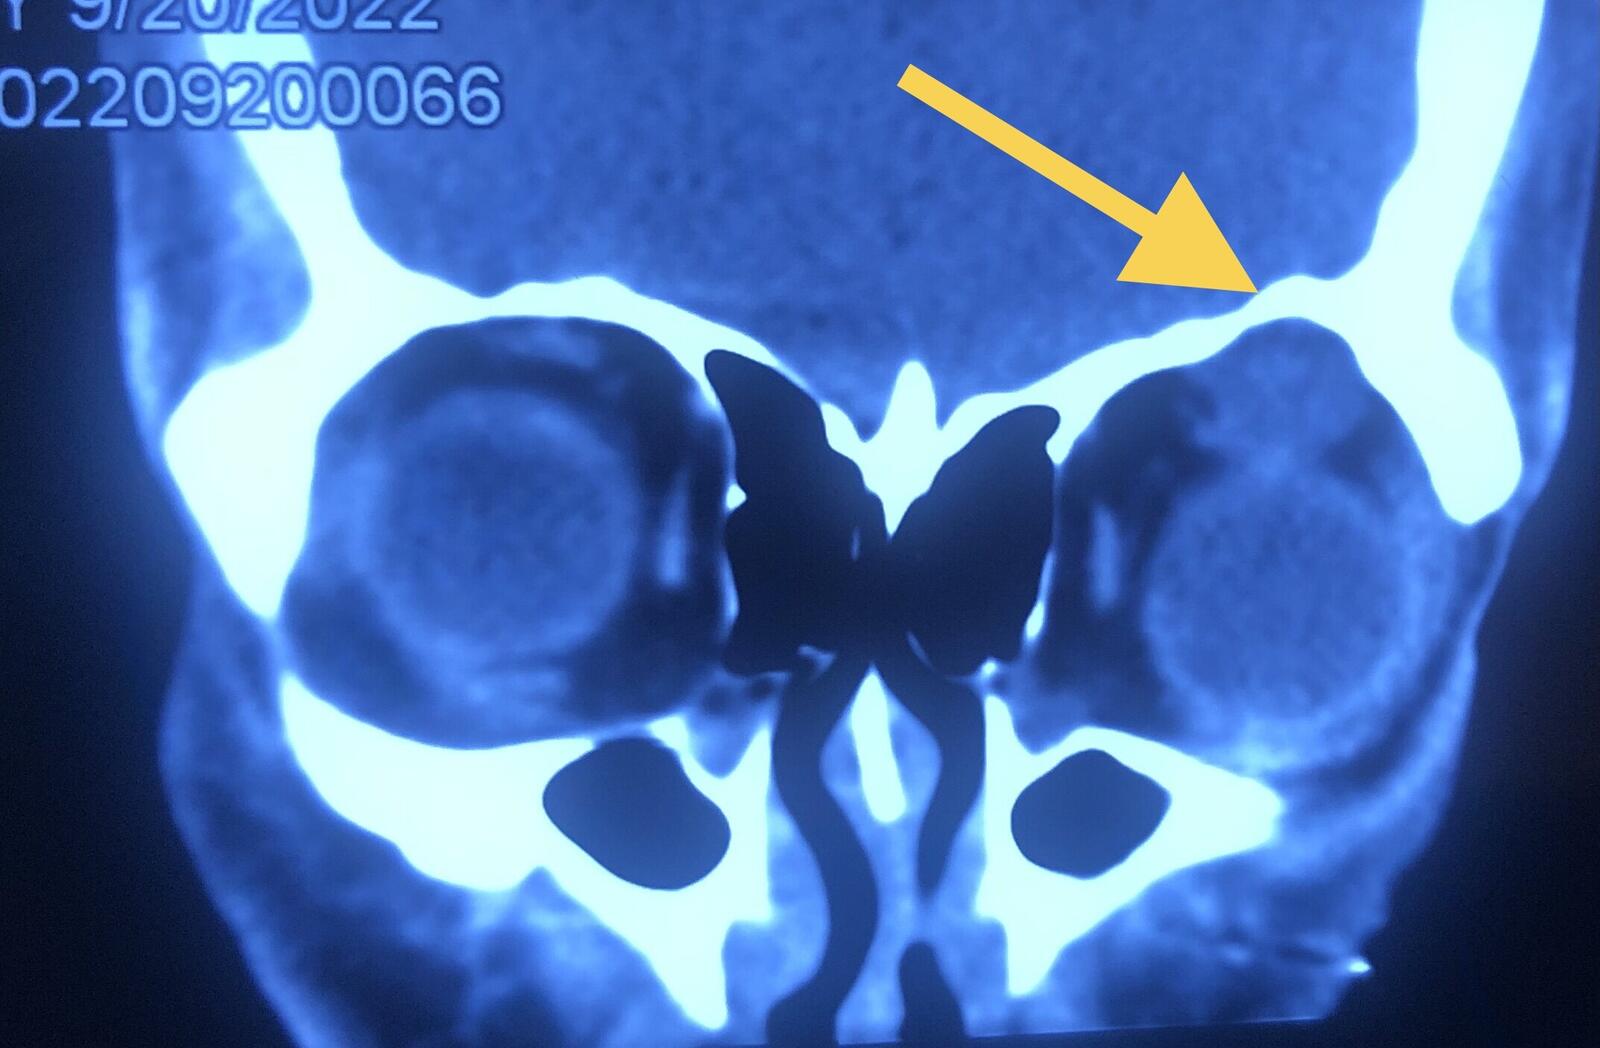

影像学显示肿物呈现不规则、结节状。

箭头处眶顶骨质压迫吸收